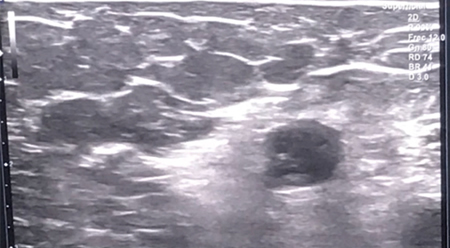

Previo a la técnica, se procede primero a la realización de un bloqueo axilar ecoguiado del miembro superior izquierdo con lidocaína 2 %. Posteriormente y tras comprobar la eficacia del bloqueo, se realiza la infiltración en el cuerpo de los neuromas. Dicha infiltración se realiza de forma ecoguiada, bajo visión directa en plano. Para ello se ubica la sonda lineal de alta frecuencia sobre las prominencias óseas inicialmente dolorosas de la paciente hasta identificar los cuerpos de los neuromas, visibles como estructuras redondeadas hipoecogénicas bien definidas. Tras su identificación, se introduce la aguja en plano hasta contactar con el cuerpo del neuroma, infiltrando en su interior un volumen de 3 ml de fenol 6 % acuoso. Este procedimiento se repite en cada uno de los neuromas previamente identificados, y posteriormente se cita a la paciente para control en consulta al mes.

Fig. 3. Visión ecográfica durante el procedimiento de uno de los neuromas tratados mediante neurólisis